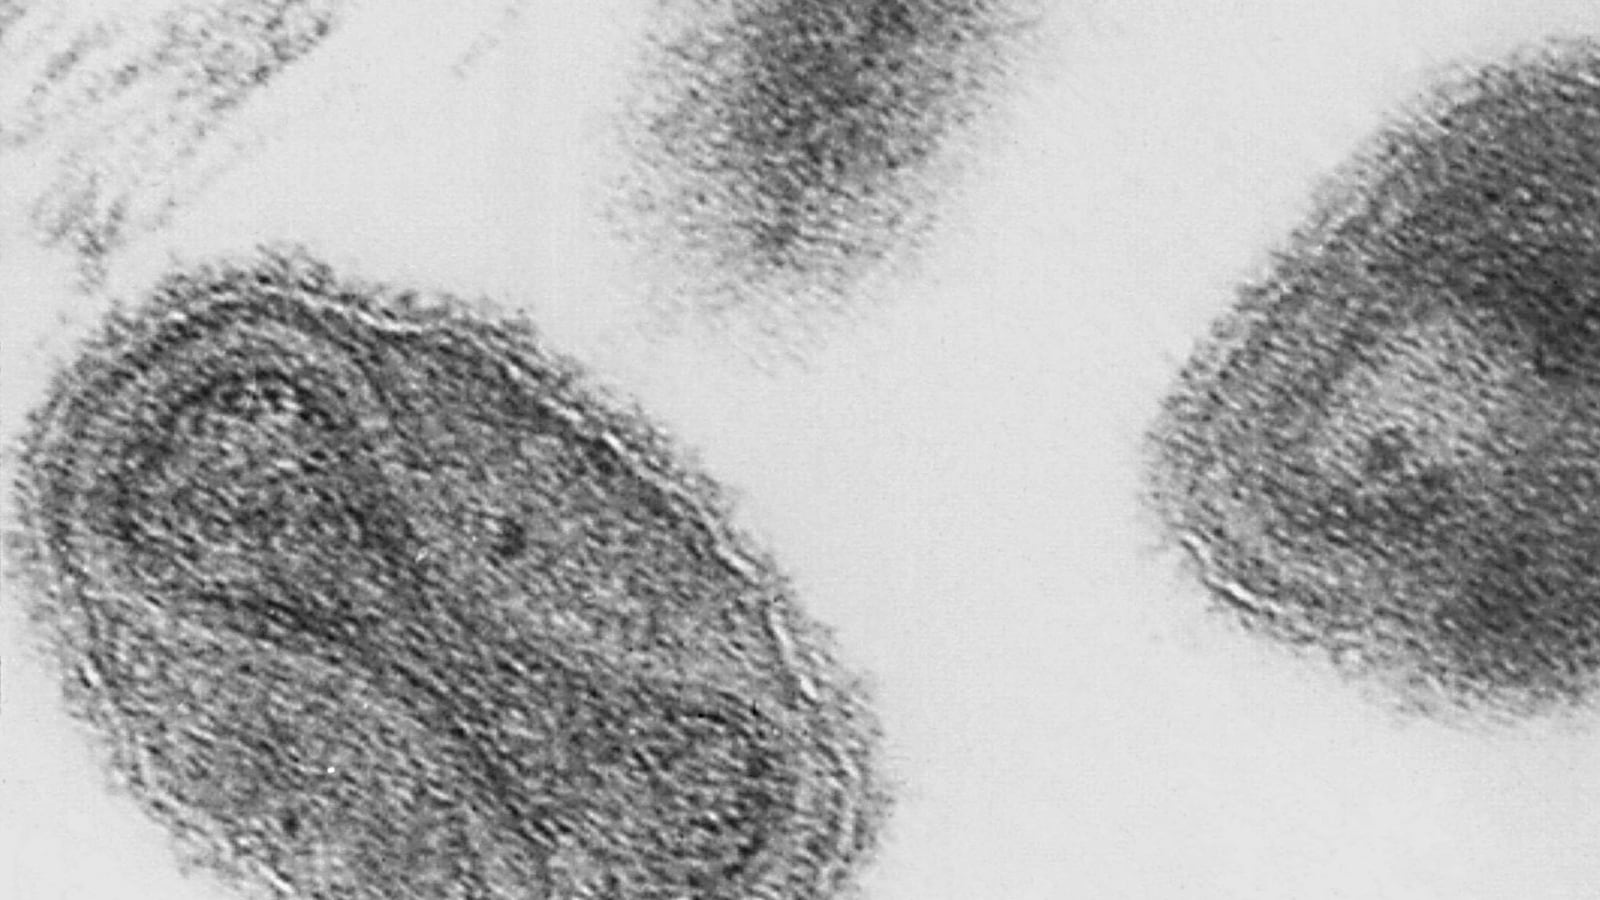

Beware of opening unmarked boxes because they may be filed with history's most deadly diseases. A scientist cleaning out a storage room in a National Institutes of Health building in Maryland discovered vials of freeze-dried smallpox virus from the 1950s—the first time an unaccounted for sample has been discovered. (The vials were intact and sealed.) Smallpox was declared to be eradicated in the 1980s, and the only known samples are under heavy security in Atlanta—where the samples have now been transferred—and Russia. "We don't yet know if it's live and infectious," an official at the Centers for Disease Control director said.